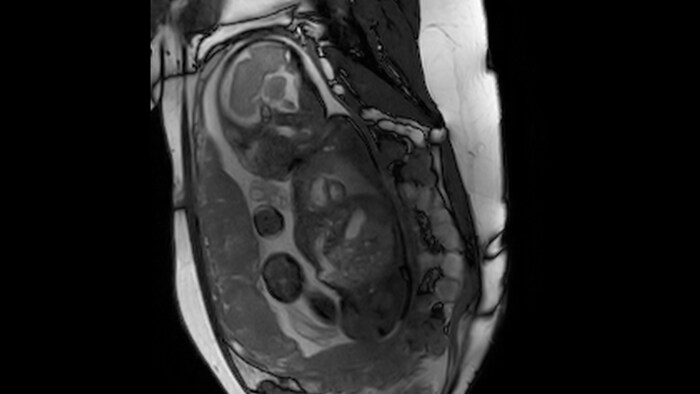

Fetal cardiac imaging examples, gestational age 33-36 weeks.

Short axis view, 1.5T

Short axis view, 3.0T

Four chamber view, 1.5T

Four chamber view, 3.0T